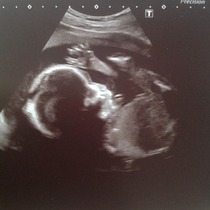

Well, had the scan yesterday and got some very cute photos, which I am attaching - one of his little foot, which is apparently 3cm long already! And he is definitely a boy!

His measurements are all spot on, and mostly his organs look good, but they were a bit concerned about his bowel which looked 'a bit bright' around the edges on the screen, so I am being referred to a consultant at the FMU.

They asked if I'd had any bleeding, as apparently the baby can ingest blood in the amniotic fluid which can make the bowel look bright, but I've not had any bleeding all pregnancy as far as I know (tho DH did point out that all my knickers are black - but I have checked every time I've wiped since October.) They said it was borderline whether or not it was actually a problem, but they would rather be over-cautious. However, they said lots of the doctors are on holiday next week because of half term, so god knows how long I will have to wait to be seen.

Bluebel those are lovely pics. Please don't talk to Dr Google. He always has the worst prognosis. Go with the professional assurances that all is ok.

They are beautiful photos!! I agree, never look up on google because it'll say so many different problems and you'll worry yourself silly! Im sure baby is okay Smile